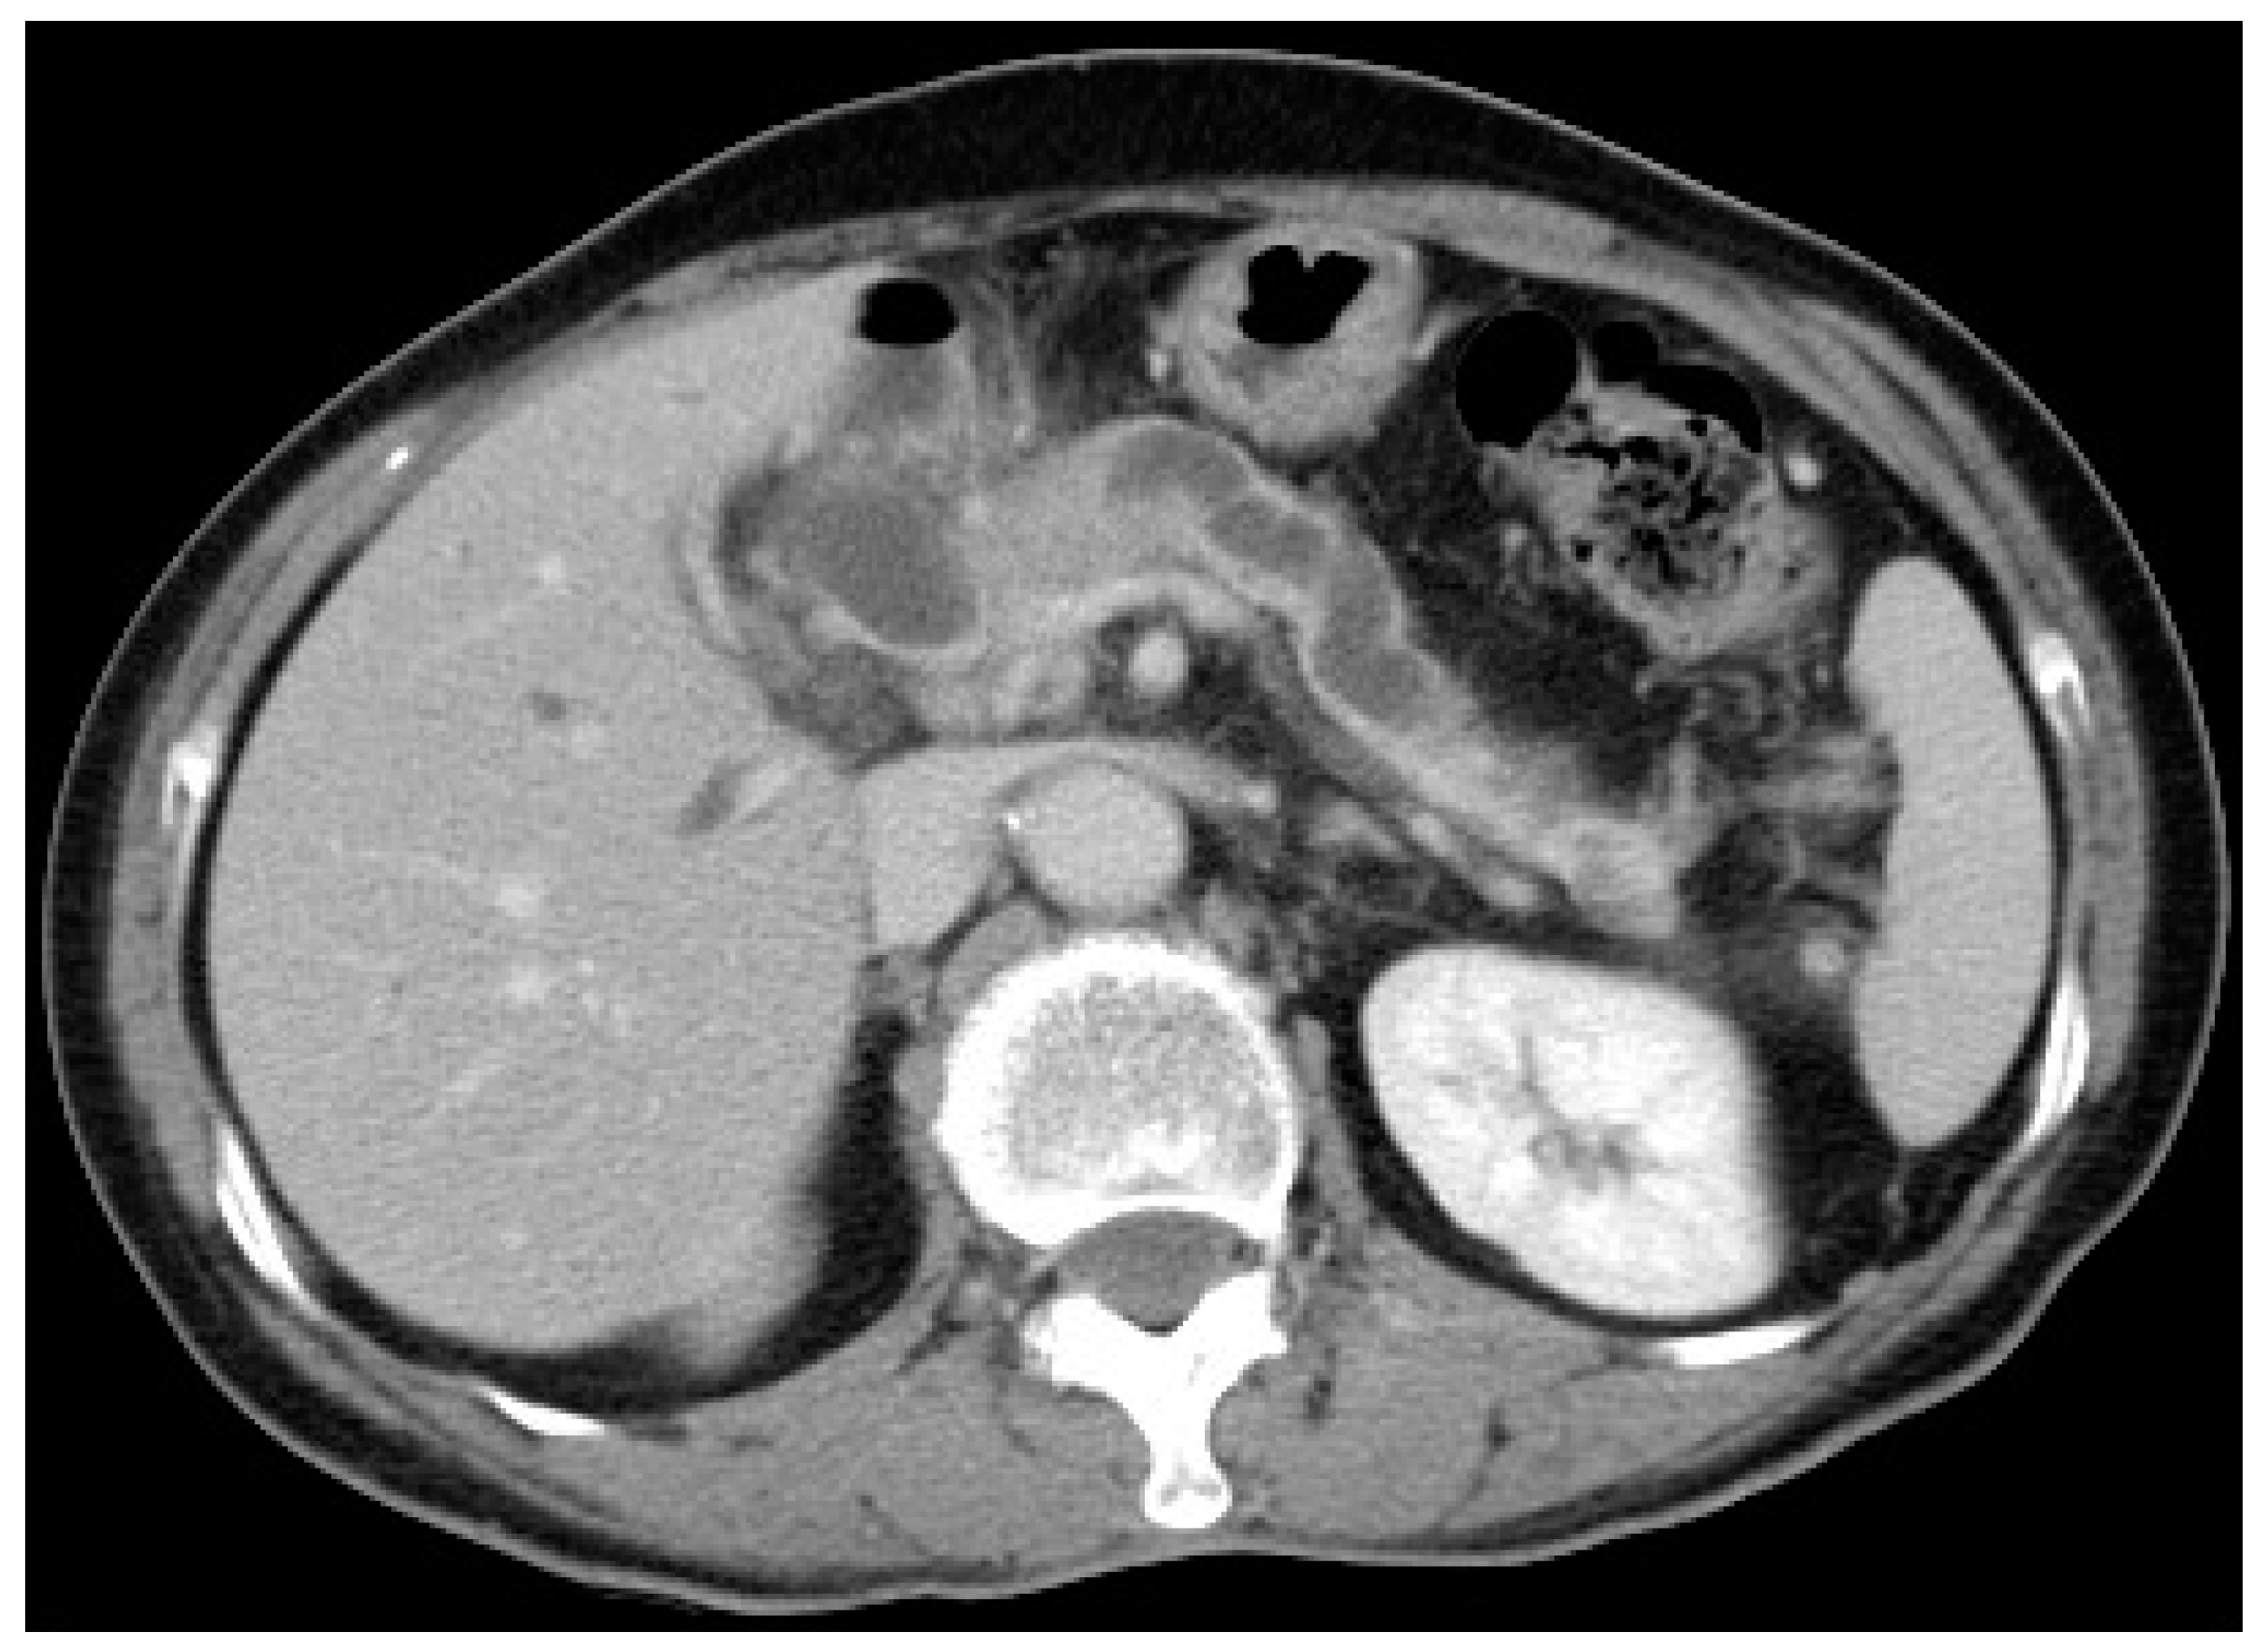

4.1. Cholangiogram Appearance, Brush Cytology and Transpapillary Biopsy

6.2. Endoscopic Ultrasound